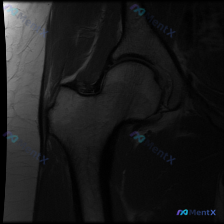

最近看到一个髋关节病例,临床怀疑盂唇病变,但提供的单张MRI-T1冠状位影像未发现明确异常。影像显示股骨头形态基本圆滑,与髋臼窝对合良好,骨髓信号均匀,未见明显的骨髓异常或结构破坏。 大家来讨论一下: 1. 这种情况下还需要做哪些检查来明确诊断? 2. 可能的诊断方向有哪些? 3. 单序列MRI的局...

看到一个髋关节MRI病例,单幅冠状位T2加权像显示髋臼外上缘盂唇有局灶性高信号改变。正常情况下,盂唇在T2加权像上应该是低信号的。大家看看这个高信号更可能是盂唇撕裂还是退变?还需要补充哪些序列的图像来明确诊断?

看到一份髋关节MRI分析材料,患者临床怀疑盂唇病变,但单幅冠状位T2序列显示: - 髋关节解剖结构完整,骨髓信号均匀 - 关节间隙清晰,软骨轮廓连续 - 髋臼盂唇未见明显形态异常或高信号撕裂影 - 关节周围软组织无明显水肿、萎缩或积液 这种影像阴性但临床高度怀疑的矛盾,大家怎么看?单张T2像能完全排...